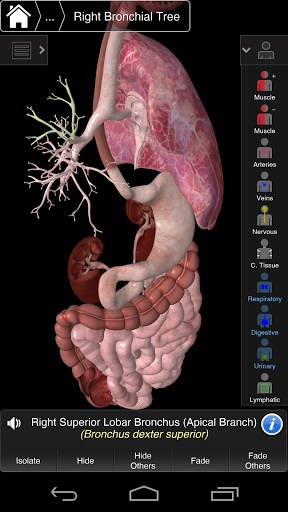

Essential Anatomy 3 représente la toute dernière technologie 3D révolutionnaire et un design innovant. Un moteur graphique 3D de pointe, construit sur mesure par 3D4Medical à partir de zéro, alimente un modèle anatomique très détaillé et fournit des graphiques de qualité exceptionnelle qu'aucun autre concurrent ne peut atteindre.

L'application représente une approche unique à l'apprentissage de l'anatomie générale. Les graphismes sont inégalés et rendent l'apprentissage, grâce à l'utilisation de contenu informatif et de fonctionnalités innovantes, une expérience riche et engageante.

Cette application comprend l'anatomie essentielle pour 10 systèmes:

⁃Respiratoire

⁃Digestif

⁃Urinaire

⁃Lymphatique

Essential Anatomy 3 est réactif, visuellement magnifique et sans effort. L'application est entièrement 3D, ce qui signifie que vous pouvez voir n'importe quelle structure anatomique dans l'isolement, ainsi que de n'importe quel angle.

---- Plus de 4000 structures anatomiques très détaillées